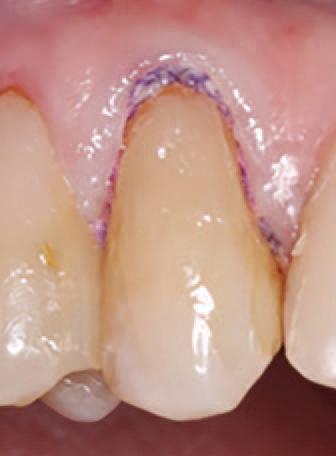

To improve isolation and soft tissue access, a retraction cord was placed before initiating the procedure (Fig. 2). The tooth was evaluated using a caries indicator dye (Kuraray Noritake Dental), helping to identify any remaining infected tissue beneath the dislodged composite (Fig. 3). Decay removal was completed with a diamond bur, and the enamel was bevelled using a starburst pattern to enhance aesthetic blending (Fig. 4). This preparation design was chosen for visual integration rather than bond strength enhancement.

2. Placement of retraction cord to improve isolation and access to the cervical area prior to preparation.